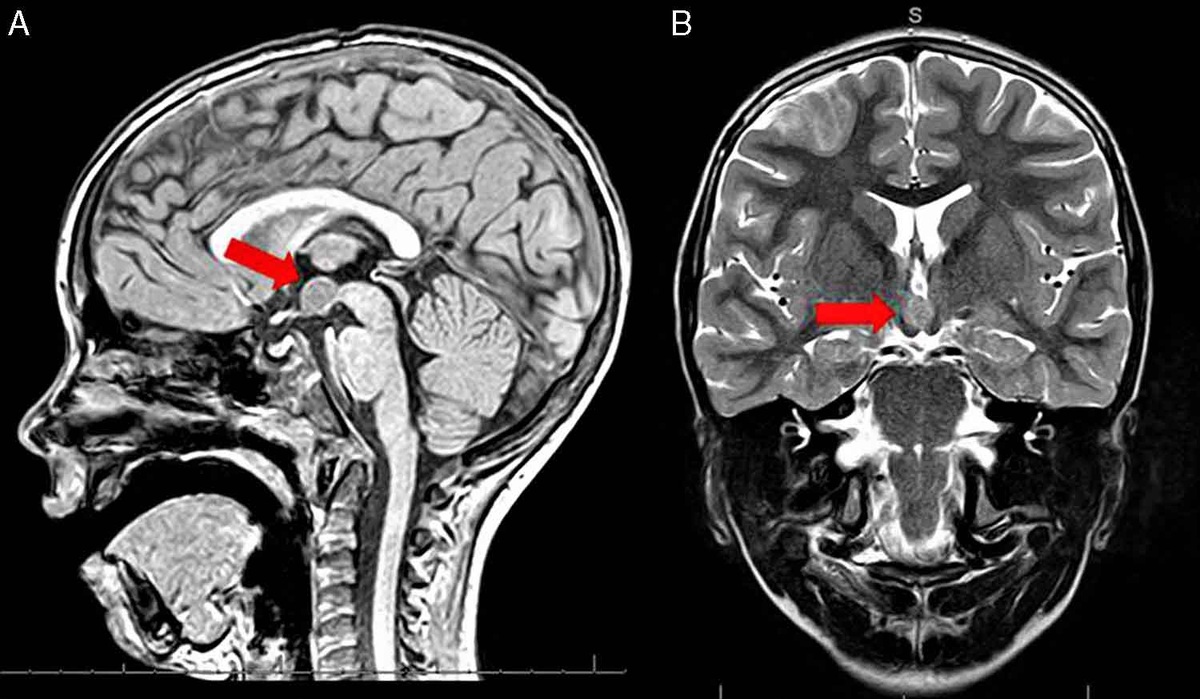

3. Ликвородинамические нарушения

Если на МРТ врач видит расширение желудочков мозга или субарахноидальных пространств.

• Суть: Это признаки нарушения оттока спинномозговой жидкости (ликвора). После 50 лет это часто связано с шейным остеохондрозом или перенесенными ранее травмами.

• Особенность: Боль обычно «распирающая», усиливается утром и при наклонах головы вниз.